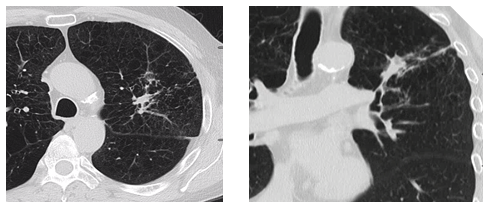

Figure A: Pre-treatment CT and PET-CT.

A 61year­old Caucasian male recent smoker with severe emphysema, but good functionality, presented for evaluation of a recently discovered left lung lesion. Pertinent history included a 40 pack­year smoking history, right lung wedge resection for an abnormal lung lesion on chest x-ray 6years earlier (pathology showed scar tissue) and a family history positive for lung cancer. On exam, Karnofsky index was 90% and PFTs revealed a FEV1 of 1.7l and a DLCO of 60% predicted. Resting O2 saturation was 94% and the physical exam was unremarkable. Radiological studies included a chest CT scan showing a 1.2cm spiculated lesion and a PET-CT scan showing a lesion with SUVmax of 3.2, with no other areas of increased SUV uptake.

Upon evaluation Radiation Oncology agreed SBRT without biopsy was a valid treatment alternative to surgery with a preceding biopsy.9 Repeat CT and PET scans showed the lesion was expanding and demonstrated increasing PET positivity with a maximum SUV of 4.4 making malignancy very likely, and per NCCN guidelines should be resected without biopsy due to it’s baseline size and interval enlargement. This approach lacked a tissue confirmation of malignancy but the positive and increasing metabolic activity on PET scan, which are used to aid in the diagnosis of moderate risk lesions in the NCCN algorithm, did provide additional confidence in the diagnosis and course of action. The lesion, assumed to be a stage IA non-small cell lung cancer, was treated with SBRT to 48Gy in four fractions every otherday using 10 static IMRT fields with 6 MV photons based on 4D CT for treatment planning. The patient tolerated the procedure well and was scheduled for routine three monthly follow up visits with imaging.